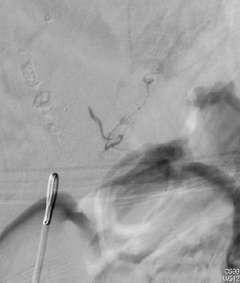

On the other hand, most dural or epidural AVFs are curable by surgery or catheter embolization. Our experience clearly shows “the sooner the treatment the better the outcome”. In our institution, minimally invasive catheter embolization was feasible in 75% of dural AVF cases. In the rest of 25% cases, surgical resection was performed. Both treatment methodologies result in a very high cure rate.

Figure 4: Catheter Embolization of a Spinal Dural AVF.